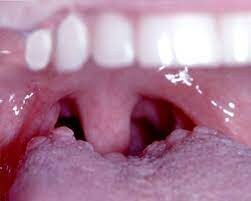

If your wisdom teeth have started to come in, you may notice that a loose flap of gum tissue has developed around them. This piece of tissue is known as an operculum, and it often develops over partially erupted teeth or teeth that do not have enough room to come in.

Learn more about issues with operculums and why they sometimes need removing.

Why Can Operculums Be a Problem?

While some operculums only partially cover a wisdom tooth, some may cover much of the chewing surface. If the flap is large, you can have an increased risk of biting the adjacent cheek tissue or the operculum itself.You can keep your enamel and attached gingiva clean with both brushing and flossing.

Operculums, on the other hand, can be difficult to keep clean since they are in the back of the mouth and because the loose tissue may trap bacteria and food debris.

If too much debris is trapped, you can develop pericoronitis, which is an inflammatory condition.  People with pericoronitis can experience bad breath, pus, and pain when eating or swallowing. If you do not treat the pericoronitis, you can experience lymph node and facial swelling.